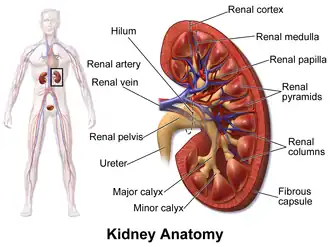

Renal cortex

Kidney anatomy, with renal cortex labeled at top. | |

The renal cortex is the outer portion of the kidney between the renal capsule and the renal medulla.[1] In the adult, it forms a continuous smooth outer zone with a number of projections (cortical columns) that extend down between the pyramids. It contains the renal corpuscles and the renal tubules except for parts of the loop of Henle which descend into the renal medulla. It also contains blood vessels and cortical collecting ducts.

The renal cortex is the part of the kidney where ultrafiltration occurs.[2] Erythropoietin is produced in the renal cortex.[3]

Kidney